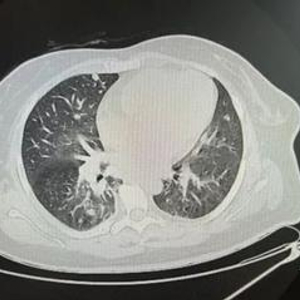

检查提示,杨女士总胆红素超300μmol/L(参考范围:5.13~22.24μmol/L),肝脏重度肿大,肝内多发占位,转移瘤考虑;肺部提示,两肺多发结节灶,转移瘤考虑;腹部B超提示,胆囊实质性占位,胆囊癌考虑,最终诊断为胆囊恶性肿瘤IV期,没有手术、化疗等机会,只能止痛姑息对症治疗,预后非常差。